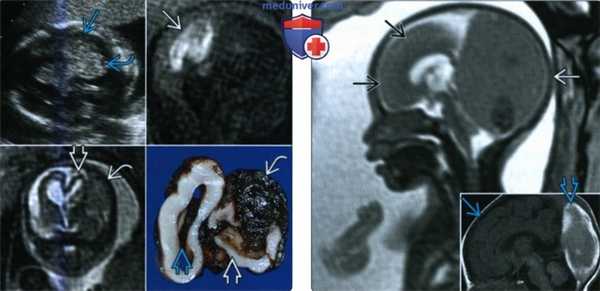

(Слева) При УЗИ в косой аксиальной плоскости у плода виден один из наиболее тяжелых вариантов аномалии. Маленький мозжечок лишен характерных признаков. Обратите внимание на выраженную вентрикуломегалию. Показан серп мозга

(Справа) При МРТ у плода выявляются аналогичные пороки развития: маленький мозжечок, лишенный характерных особенностей, и выраженная вентрикуломегалия. Горизонтально расположенные листки мозжечка видны не всегда, их визуализация зависит от ограничений поля зрения, выбранной последовательности и разрешения.

(Слева) На фотографии нижней поверхности патологоанатомического препарата головного мозга видны горизонтальные листки мозжечка. Они не были заметны при УЗИ или МРТ из-за ограниченных полей зрения и разрешения. Размеры мозжечка крайне малы по сравнению со стволом мозга и головным мозгом в целом.

(Справа) При МРТ на Т2-ВИ во фронтальной плоскости у плода с РЭС и комплексом AVID визуализируются сопутствующие пороки развития: слияние столбов свода мозга, МПК и дисплазия коры больших полушарий головного мозга (патологический рисунок сильвиевой борозды и извилин).

(Слева) При патологоанатомическом исследовании младенца, погибшего через несколько часов после родов, обнаруживается слияние полушарий мозжечка и зубчатого ядра, а также IV желудочек в форме бриллианта. Это классические находки при РЭС.

(Справа) При МРТ в аксиальной плоскости у ребенка с РЭС видно слияние зубчатых ядер, вследствие которого IV желудочек имеет патологическую форму.